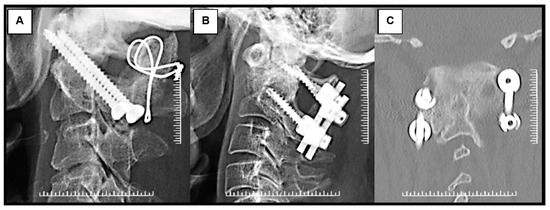

2.3. Surgical Fixation Techniques

Figure 1. Radiographic images of nonunited type II odontoid fracture with atlantoaxial instability. Atlantoaxial instability with cervical myelopathy caused by nonunited type II odontoid fracture (Red arrows): (A) lateral plain radiograph; (B) coronal CT image; (C) sagittal MR image.